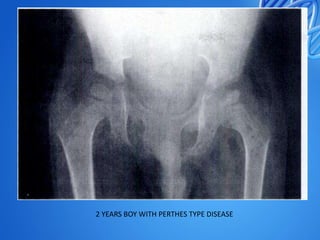

2 YEARS BOY WITH PERTHES TYPE DISEASE

2 YEARS BOYWITH PERTHES TYPE DISEASE

Perthes type hip epiphysio-metaphysealtuberculosis of the left proximal femur (a, b). After joint debridement, the child was immobilized with cast for 6 weeks under cover of triple chemotherapy (12 months). Tuberculosis healed without joint destruction, though residual coxa magna deformity was present (c)